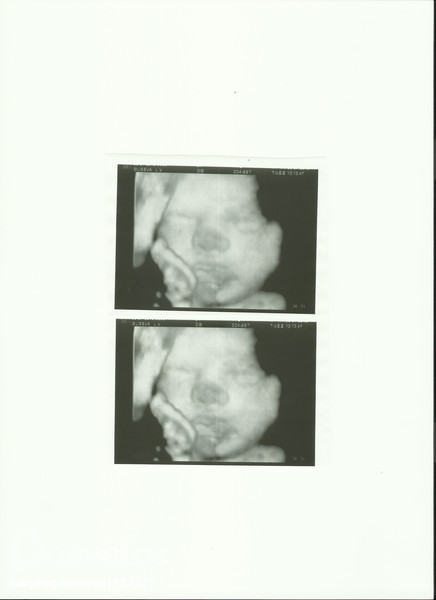

А вот наша мордашка... Носик темнее, так как в стенку матки уперся им... не хотел показываться, но 3d всесильно!!!